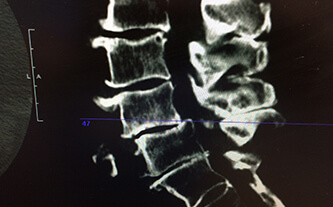

A Review of Conservative Options in the Treatment and Management of Lumbar Spinal Stenosis

What’s the Best Way to Manage Back Pain? Low back pain can be a serious impairment on normal daily function and has become one of the most common reasons that patients visit a physician, (Stuber, Sajko, & Kristmanson, 2009). While there are various direct and idiopathic causes for low back pain and dysfunction, this examination…